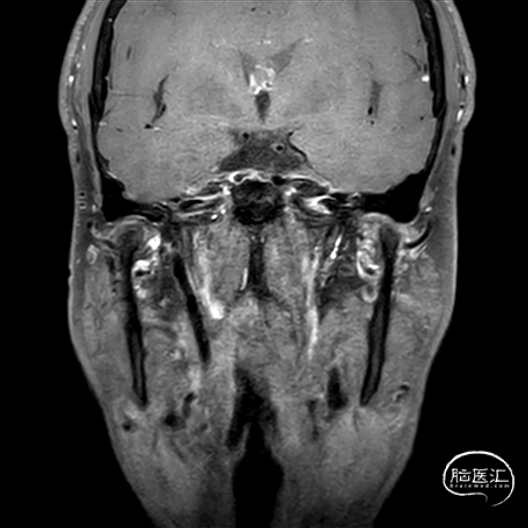

现病史:患者今年2月份出现头晕伴左侧肢体无力,MR诊断为脑干及双侧小脑梗死,治疗后好转。一直口服阿司匹林+波立维治疗;4月份患者出现视物成双伴口角歪斜,MR诊断为右侧小脑及左侧丘脑梗死。

2024年2月1日

2024年4月17日